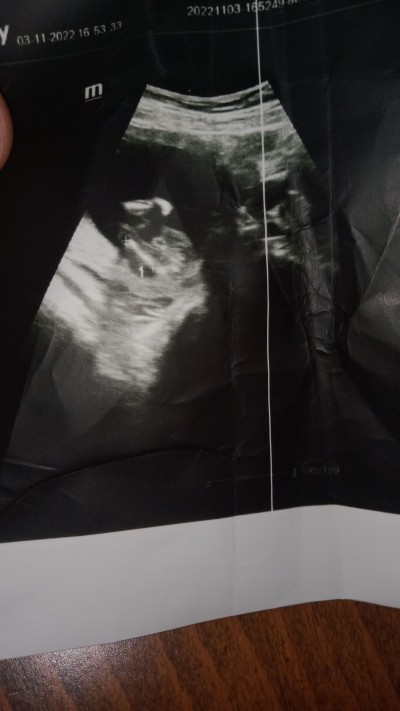

Cinsiyet erkek mi kızmı

Doktor net bişey demedi

Gebelik haftası

15 hafta

Erkek gibi sanki

Kesinlikle erkek bencede

Net bişe söylemiyor doktorum erkeğe benziyor diyor sadece